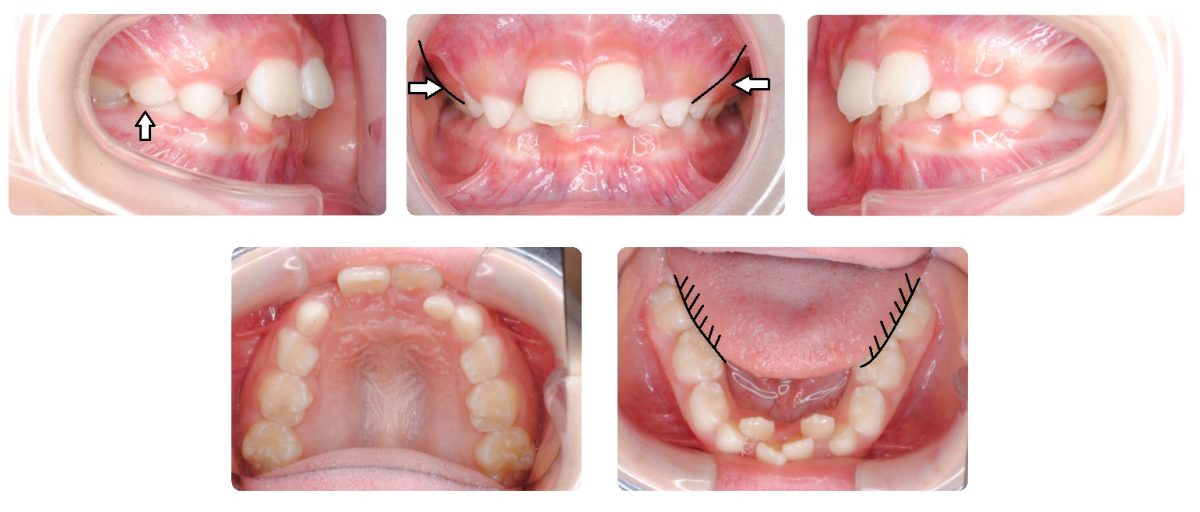

今回紹介する症例は小児の混合歯列期です。 ”下顎の前歯の歯並びがガタガタ” だということで来院されました。

初診時ではほとんどの小児矯正の主訴が前歯に関するものなのですが、この症例では下顎の前歯に加えて下顎の側方歯が殆ど見えない(矢印)ほど全体のかみ合わせが非常に深い(過蓋である)ことがわかります。

さらには下記の正面写真の矢印で図示しましたように外部から内側へと押されたような上顎骨が独特な形状をしております。下顎を診てみますと歯列が非常に狭くなっており舌が常に上から覆い被さっている状態です。